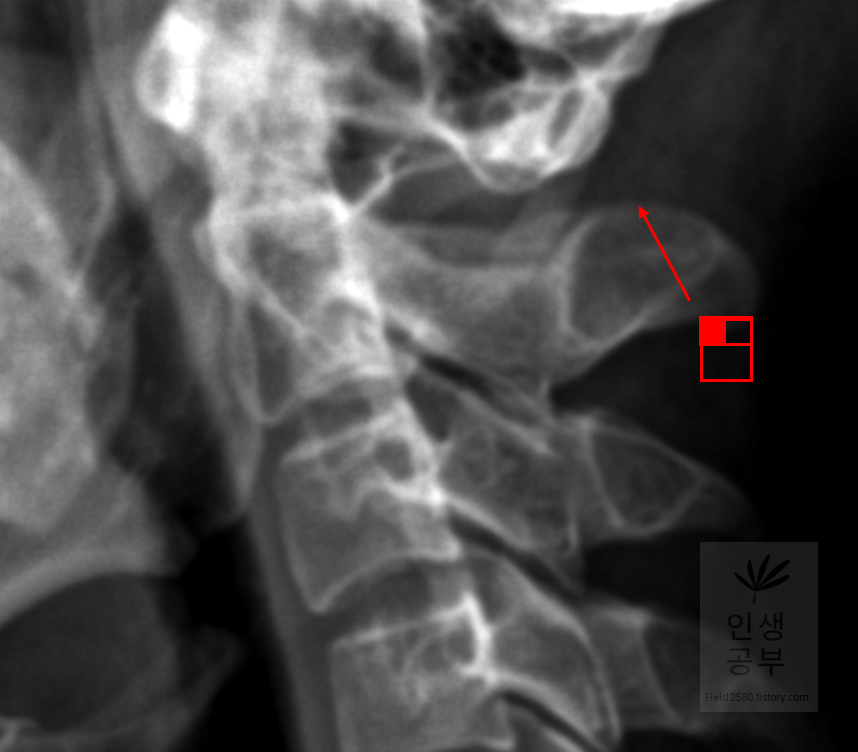

선 긋기를 이용해서 Cobb각을 그린다고 가정했을 때 측정하려고 하는 곳을 처음에 누르고 드래그로 쭉 끌어다주면 위와 같은 선이 생기고 선의 길이가 자동으로 측정됩니다. 첫 번째 목뼈(C1) 선을 그리기 위해 제일 튀어나온 앞쪽 부분 가운데 지점에(Center of Anterior arch) 점을 찍어줍니다. 후궁(Posterior arch) 제일 좁은 부위 가운데 지점에 점을 찍어줍니다. 두 점을 연결해주는 선을 그어줍니다. 이 선 이름을 고리 뼈 선(APL : Atlas Plane Line)이라고 합니다. 점은 조금 더 정확하기 위해서 하는 것이 찍어도 되고, 점을 찍지 않은 상태에서 선을 그으셔도 무방합니다.

일곱번째 목뼈 추체 밑면(Inferior endplate of C7)과 평행한 선을 그어줍니다.

위쪽에 있는 선은 첫 번째 목뼈(C1) 선을 그리기 위해 제일 튀어나온 앞쪽 부분 가운데 지점에(Center of Anterior arch)에서 시작해서 후궁(Posterior arch) 제일 좁은 부위 가운데를 지나는 선이 되도록 이동해줍니다. 선 이름을 고리 뼈 선(APL : Atlas Plane Line)이라고 합니다. 점은 조금 더 정확하기 위해서 하는 것이 찍어도 되고, 점을 찍지 않은 상태에서 선을 그으셔도 무방합니다. 아래쪽에 있는 선은 일곱번째 목뼈 추체 밑면(Inferior endplate of C7)과 평행하게 선을 맞춰줍니다. 노란색 글자와 숫자가 아래줄 맞춰 준 곳에 있는데 A는 Angle 각도이고 옆에 있는 숫자가 Cobb 각입니다.

목의 정렬을 알아보기 위해서 목뼈의 선들을 연결해서 그어보는 방법에 대해서 알아보겠습니다. 도구 상자에서 빨간색네모상자 안에 있는 물결무늬 모양의 버튼을 눌러줍니다.

목뼈 추체 제일 앞쪽에 있는 선을 따라서 그어줍니다.

목뼈 추체 뒷면을 따라서 선을 그어줍니다.

Spinolaminal line을 따라서 선을 그어줍니다.

극돌기(Spinous process) 끝을 따라 선을 그어줍니다. 각각의 라인의 곡선의 커브가 자연스럽게 연결되었는지 확인해 줍니다. 이처럼 연결된 선을 이용해서 각각의 뼈의 정렬을 선을 그어서 알아보고 싶으면 곡선으로 그려진 버튼을 이용해서 확인할 수 있습니다.